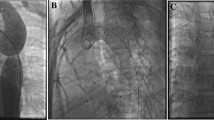

To determine normal four-extremity blood pressure (BP) in the neonatal intensive care unit (NICU) at birth and the utility of upper (UE) and lower extremity (LE) BP difference to screen for coarctation of the aorta (Co-A) and interrupted the aortic arch (IAA).

Although BP increased with gestational age (R2=0.3, P<0.0001), the pressure gradient between UE and LE did not change with gestation (P=0.68). Forty-six cases of Co-A/IAA were identified, with 92 controls. Pressure gradient was significantly higher in patients with Co-A/IAA (7.6±14.8 versus 0.4±10 mm Hg, P=0.004). However, there was overlap between cases and controls resulting in low sensitivity (41.3% with ⩾10 mm Hg gradient cutoff).

Evaluation of UE–LE BP gradient at birth is a poor screening test for Co-A/IAA with low sensitivity. Repeating four-limb BP after ductal closure at 24 to 48 h along with SpO2 screening for critical congenital heart disease may increase sensitivity.